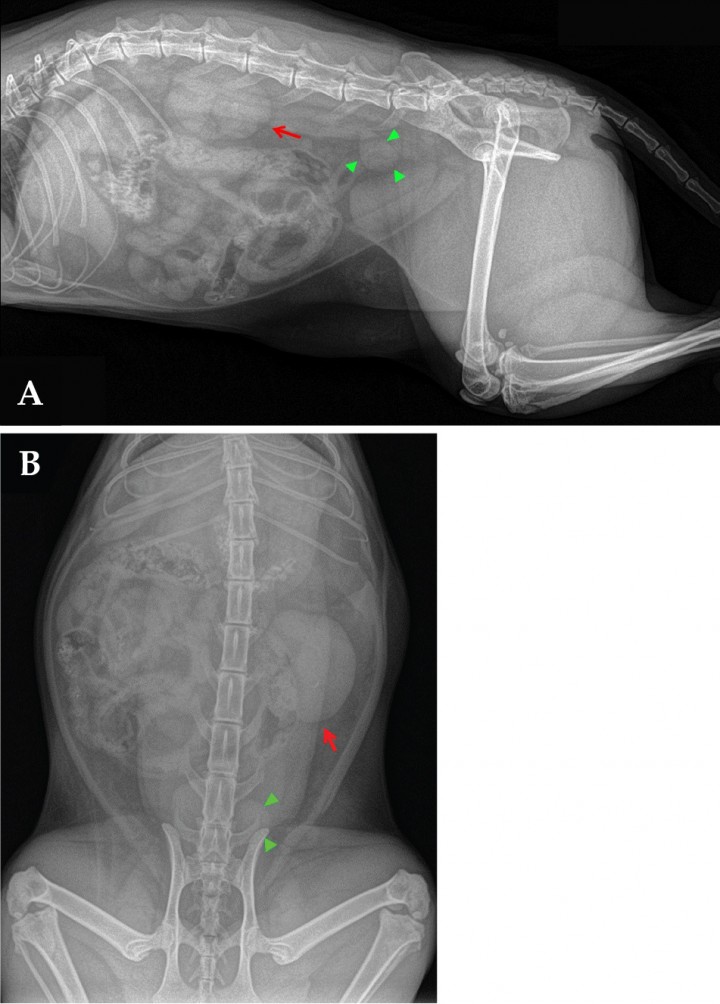

Se hizo un estudio radiológico del abdomen, con proyecciones lateral derecha (LD) y ventrodorsal (VD) (Fig. 1).

<p>(A) Proyección lateral derecha. (B) Proyección ventrodorsal de abdomen de una gata común Europeo de 2 años con un cuadro de hematuria.</p>

(A) Proyección lateral derecha. (B) Proyección ventrodorsal de abdomen de una gata común Europeo de 2 años con un cuadro de hematuria.

En la proyección LD, las anormalidades radiográficas más relevantes fueron: en la zona de localización de las siluetas renales se apreció un aumento de opacidad en el centro de las mismas y se sospechó que los márgenes de la silueta renal izquierda eran irregulares (Fig. 2A); dorsal a la vejiga de la orina se observó una zona de opacidad tejido blando anormal con forma de lágrima a la altura de la sexta vértebra lumbar (L6) (Fig. 2A).

<p>Mismas imágenes que en la Fig. 1 (A) Proyección lateral derecha. Se observan las siluetas renales superpuestas y un aumento de opacidad en el centro de las mismas. Los márgenes de la silueta renal izquierda son irregulares (flecha roja). Dorsal a la vejiga de la orina hay una zona de opacidad tejido blando anormal, con forma de lágrima, a la altura de L6 (cabezas de flecha verdes). (B) Proyección ventrodorsal de abdomen. Se observa una evidente diferencia de tamaño entre el riñón derecho (normal) y el izquierdo (aumentado de tamaño), evidenciándose de manera más clara la irregularidad de sus márgenes y una zona de opacidad mineral en la zona de proyección de la pelvis renal (flecha roja). Al igual que en la proyección lateral, se observa la misma estructura de opacidad tejido blando con forma de lágrima (cabezas de flecha verdes).</p>

Mismas imágenes que en la Fig. 1 (A) Proyección lateral derecha. Se observan las siluetas renales superpuestas y un aumento de opacidad en el centro de las mismas. Los márgenes de la silueta renal izquierda son irregulares (flecha roja). Dorsal a la vejiga de la orina hay una zona de opacidad tejido blando anormal, con forma de lágrima, a la altura de L6 (cabezas de flecha verdes). (B) Proyección ventrodorsal de abdomen. Se observa una evidente diferencia de tamaño entre el riñón derecho (normal) y el izquierdo (aumentado de tamaño), evidenciándose de manera más clara la irregularidad de sus márgenes y una zona de opacidad mineral en la zona de proyección de la pelvis renal (flecha roja). Al igual que en la proyección lateral, se observa la misma estructura de opacidad tejido blando con forma de lágrima (cabezas de flecha verdes).

En la proyección VD se visualizó una evidente asimetría entre el riñón derecho (de tamaño normal) y el izquierdo (aumentado) (ratio RI/L2 2,8, rango normal para una gata castrada 1,9-2,6), el cual además presentó bordes irregulares (Fig. 2B). Además, se apreció una zona de opacidad mineral en la zona de proyección de la pelvis renal. Asimismo, se observó, a idéntica altura que en la proyección LD, la misma estructura de opacidad tejido blando con forma de lágrima, que se proyectaba hacia el lado izquierdo (Fig. 2B).